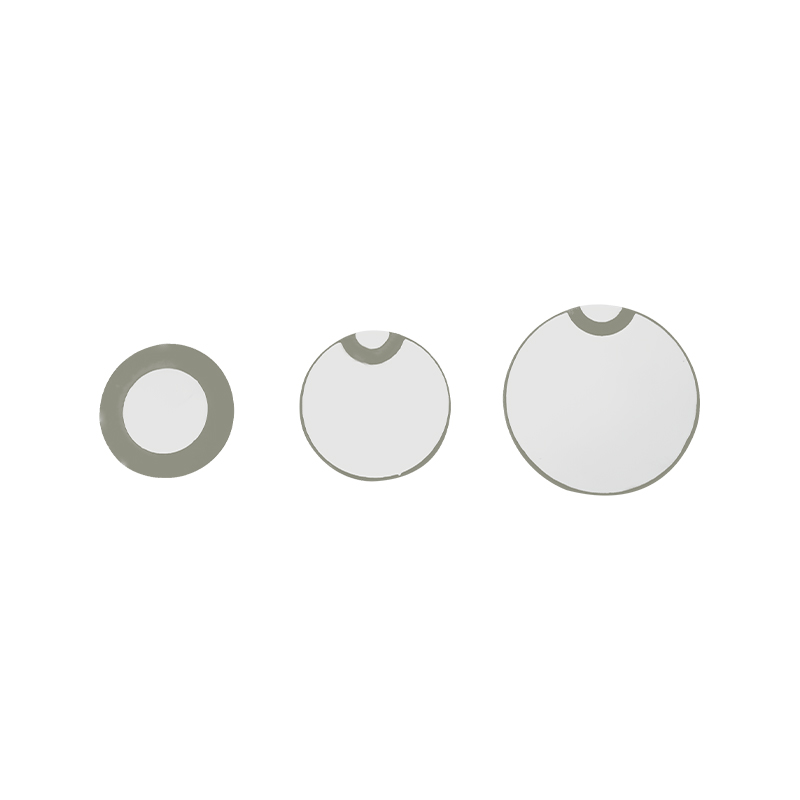

Les comprimés de nébuliseur à mailles médicales sont des composants de précision utilisés dans les dispositifs médicaux pour convertir des médicaments ou des solutions en minuscules particules d'aérosol pour le traitement de divers troubles respiratoires tels que l'asthme et la maladie pulmonaire obstructive chronique (MPOC), etc. par inhalation. La conception et le choix des matériaux de la feuille du nébuliseur sont essentiels pour garantir une administration efficace du médicament et le confort du patient. La feuille de diaphragme en acier inoxydable est percée de milliers de minuscules trous de maille de 2 à 3 µm dans la tôle d'acier grâce à une technologie de perçage laser dans un processus laser de précision, puis elle est étroitement liée à la feuille ronde en céramique piézoélectrique, qui convertit la fréquence de résonance de la feuille piézoélectrique en énergie de vibration haute fréquence via le signal de sortie de la carte de commande PCB, et décompose rapidement le médicament liquide en fines particules d'aérosol. Ces gouttelettes sont également appelées taille médiane des particules. Lorsque le pourcentage médian de la taille des particules D50 atteint > 60 % ou plus, les particules seront suffisamment petites pour pouvoir atteindre profondément les poumons jusqu'à la surface des alvéoles avec la respiration, améliorant ainsi l'efficacité d'absorption du médicament et l'effet thérapeutique. La feuille de nébuliseur à micro-mailles médicales a principalement plusieurs formes, une feuille de nébuliseur à micro-mailles en acier inoxydable, une feuille de nébuliseur médical en nickel palladium, une feuille de nébuliseur médical en polymère PI, etc. Tout ce qui précède se fait grâce à la conversion d'énergie de vibration piézoélectrique en céramique pour obtenir l'effet d'atomisation.

Le polyimide (Polyimide), appelé PI, est la meilleure performance globale des matériaux polymères organiques, il a une excellente stabilité chimique et peut résister à la corrosion d'une variété de médicaments, pour garantir l'utilisation à long terme des performances des comprimés atomisés. En outre, la stabilité thermique du film polymère PI est également excellente, avec une utilisation à long terme d'une plage de température de -200 ~ 300 ° C, une isolation élevée, une protection de l'environnement et une non-toxicité, en tant que matériau d'ingénierie spécial, largement utilisé dans les membranes de séparation à cristaux nano-liquides de la microélectronique aérospatiale et dans d'autres domaines, a été inclus au 21e siècle par les pays de l'un des matériaux d'ingénierie les plus prometteurs, et il n'est pas facile d'être déformé lors du processus de désinfection à haute température, pour garantir la réutilisation du produit ! Pour le sexe et la sécurité, nous utilisons la technologie laser pour la perforation laser, un film PI implanté entre l'acier inoxydable et la feuille piézoélectrique, l'utilisation de la technologie ultrasonique en céramique piézoélectrique afin que les gouttelettes atomisées à travers le film PI se dispersent dans l'atomisation de particules de 3 ~ 4 μm pour l'inhalation par nébulisation médicale, la sécurité de la majorité des utilisateurs aime, fait du nébuliseur avec le Le principal avantage de PI est le non-colmatage, la paroi intérieure du trou est lisse et arrondie, aucun résidu de liquide, l'atomisation fine et stable. L'atomisation est délicate et stable. Comprimés nébuliseurs à film PI, il peut prévenir efficacement les résidus de médicaments et réduire le risque de contamination croisée. Dans l'application pratique, les caractéristiques de faible consommation d'énergie des comprimés de nébuliseur à membrane polymère PI ont également été reflétées. En résumé, les comprimés de nébuliseur à membrane polymère PI, avec leurs excellentes performances et leurs avantages de conception, sont devenus un élément indispensable du domaine de la thérapie par nébulisation médicale.